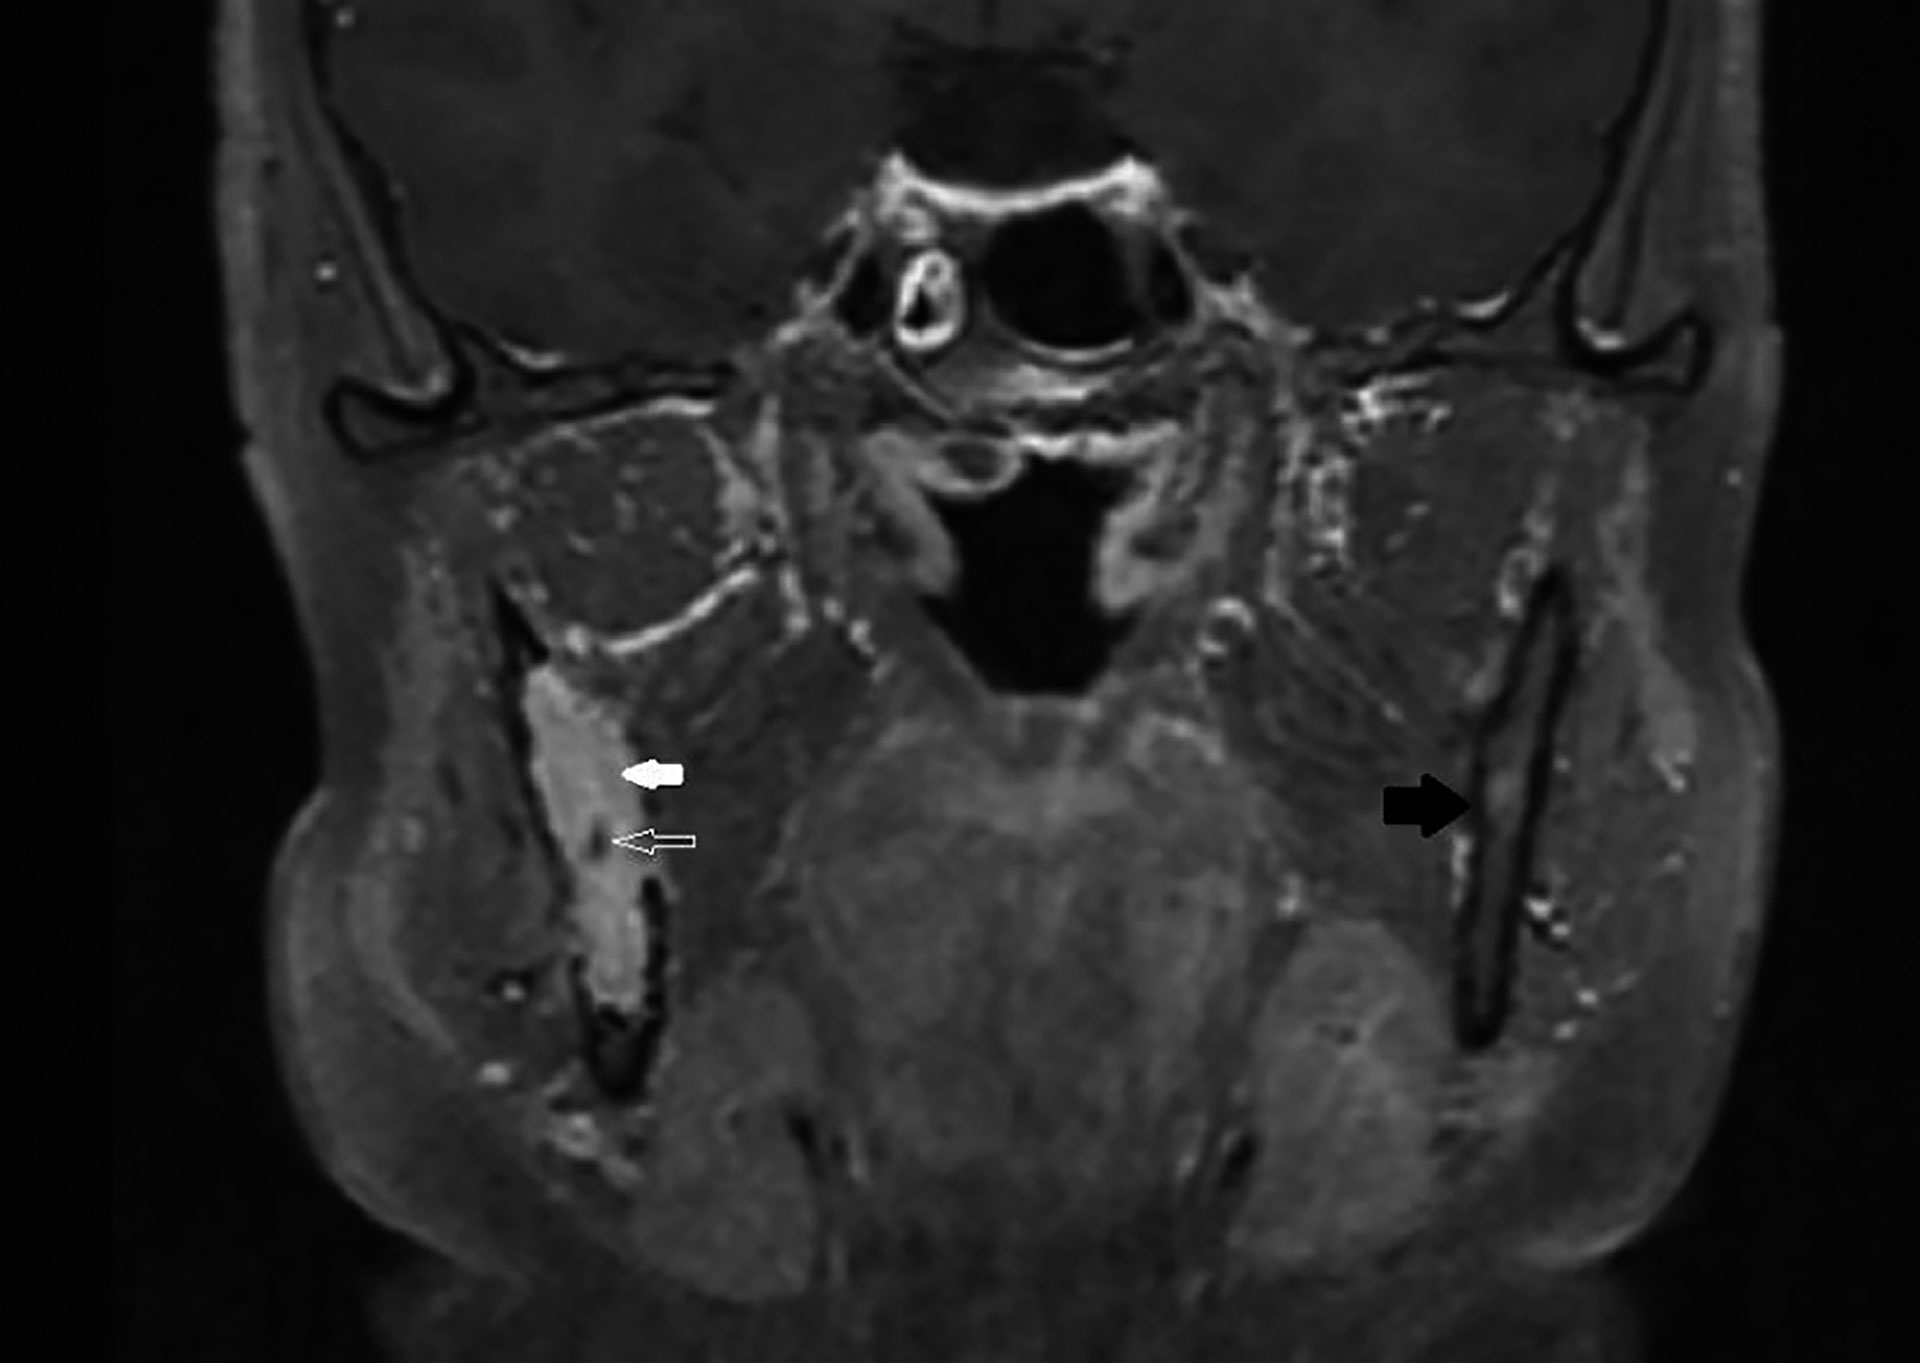

Figur 9 MR med intravenøs kontrast og fettsuppresjon. Hvit, tykk pil på solid, kontrastladende vev i marghulen som omslutter nervus alveolaris inferior (hul og hvit pil). Svart pil mot friskt kortikalt og medullært bein på kontralateral side.

MR (figur 9) viste en lobulær, solid forandring som var uendret i omfang, sammenlignet med CT-undersøkelsen tre måneder tidligere. Nervus alveolaris inferior forløp upåvirket gjennom svulsten. På steder der det manglet beindekning, var det ikke tegn til reaksjon i inntilliggende bløtvev. Radiologisk var funnene forenlig med en solid, ekspansiv, men ikke-infiltrerende svulst.